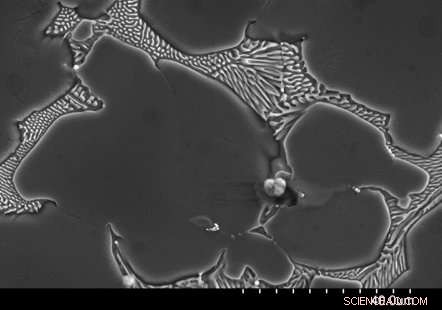

Image from electron microscope showing a large precipitate in magnesium alloy. These precipitates are dissolved through heat treatment, which substantially reduces the corrosion rate and makes the alloy very stable in the body. Credit: NYU Tandon School of Engineering